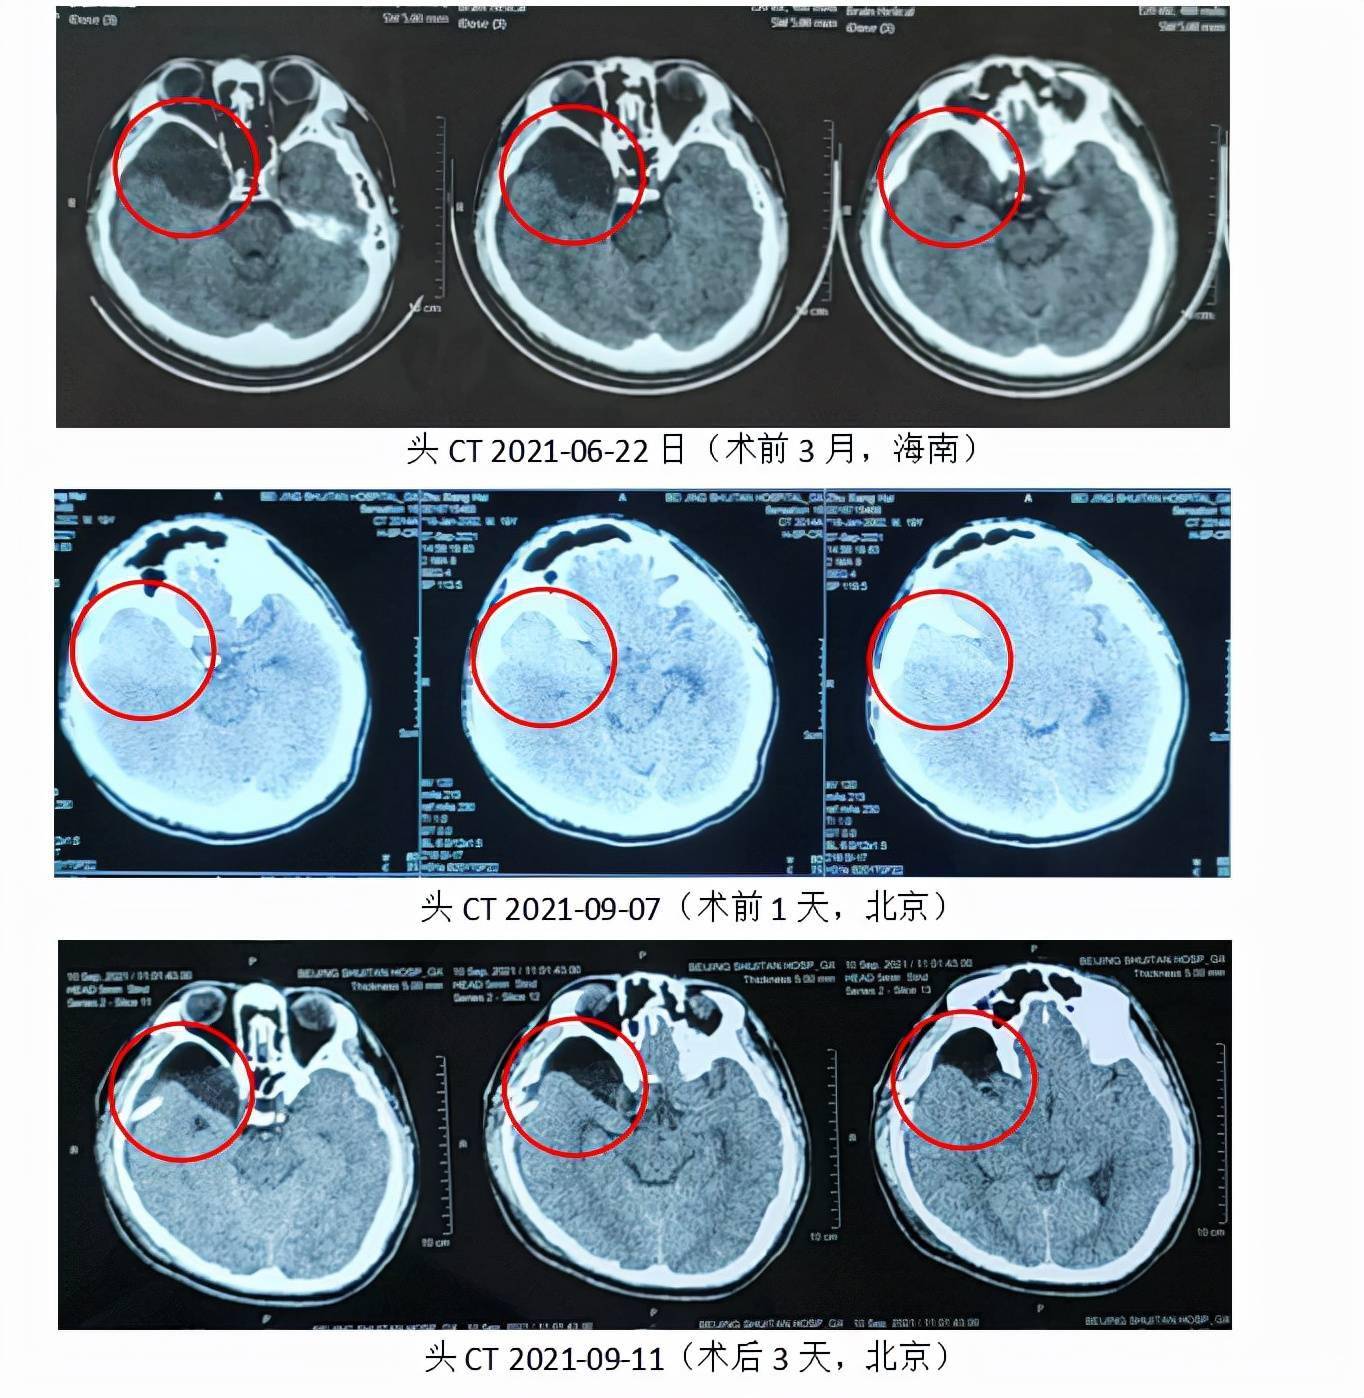

原创贺晓生教授儿童颅内巨大蛛网膜囊肿手术治疗案例

入院时患者头疼明显加重,伴恶心呕吐,头ct提示"硬膜下及蛛网膜囊肿内

贺晓生教授儿童颅内巨大蛛网膜囊肿手术治疗案例

囊肿腔腹腔分流术半年后复查ct:囊肿明显变小